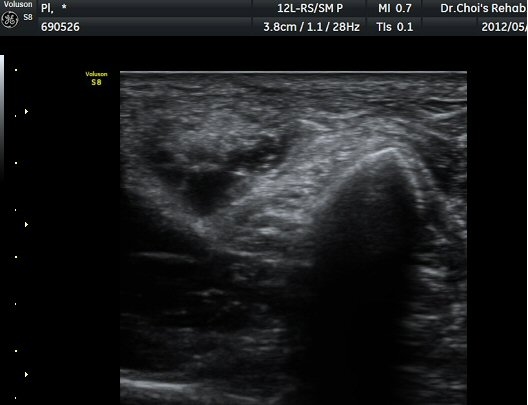

ŽÃËÁö¸¦ Á¶±Ý ´õ ¾Æ·¡·Î À̵¿ÇÏ´Ï »ÀÀÇ µÎ²²°¡ °¨¼ÒÇÏ´Â °ÍÀ» º¸°í ºñ°ñÀÇ ¸ñ ºÎÀ§¸¦ °üÂûÇϰí ÀÖÀ½À» ¾Ë ¼ö ÀÖ°í ÃѺñ°ñ ½Å°æÀº ºñ°ñ ¸ñ Ç¥Ãþ¿¡¼­ °üÂûµÈ´Ù(±×¸² 5).